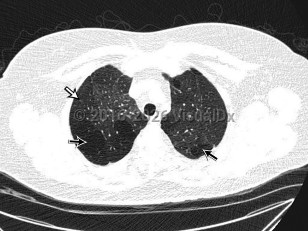

The clinical syndrome manifests as an airway obstruction, cough, and slowly progressive dyspnea (weeks to months), with radiographic examination showing normal or hyperinflation of the lungs. Tachypnea, crackles, and/or wheezing may be evident on physical examination.